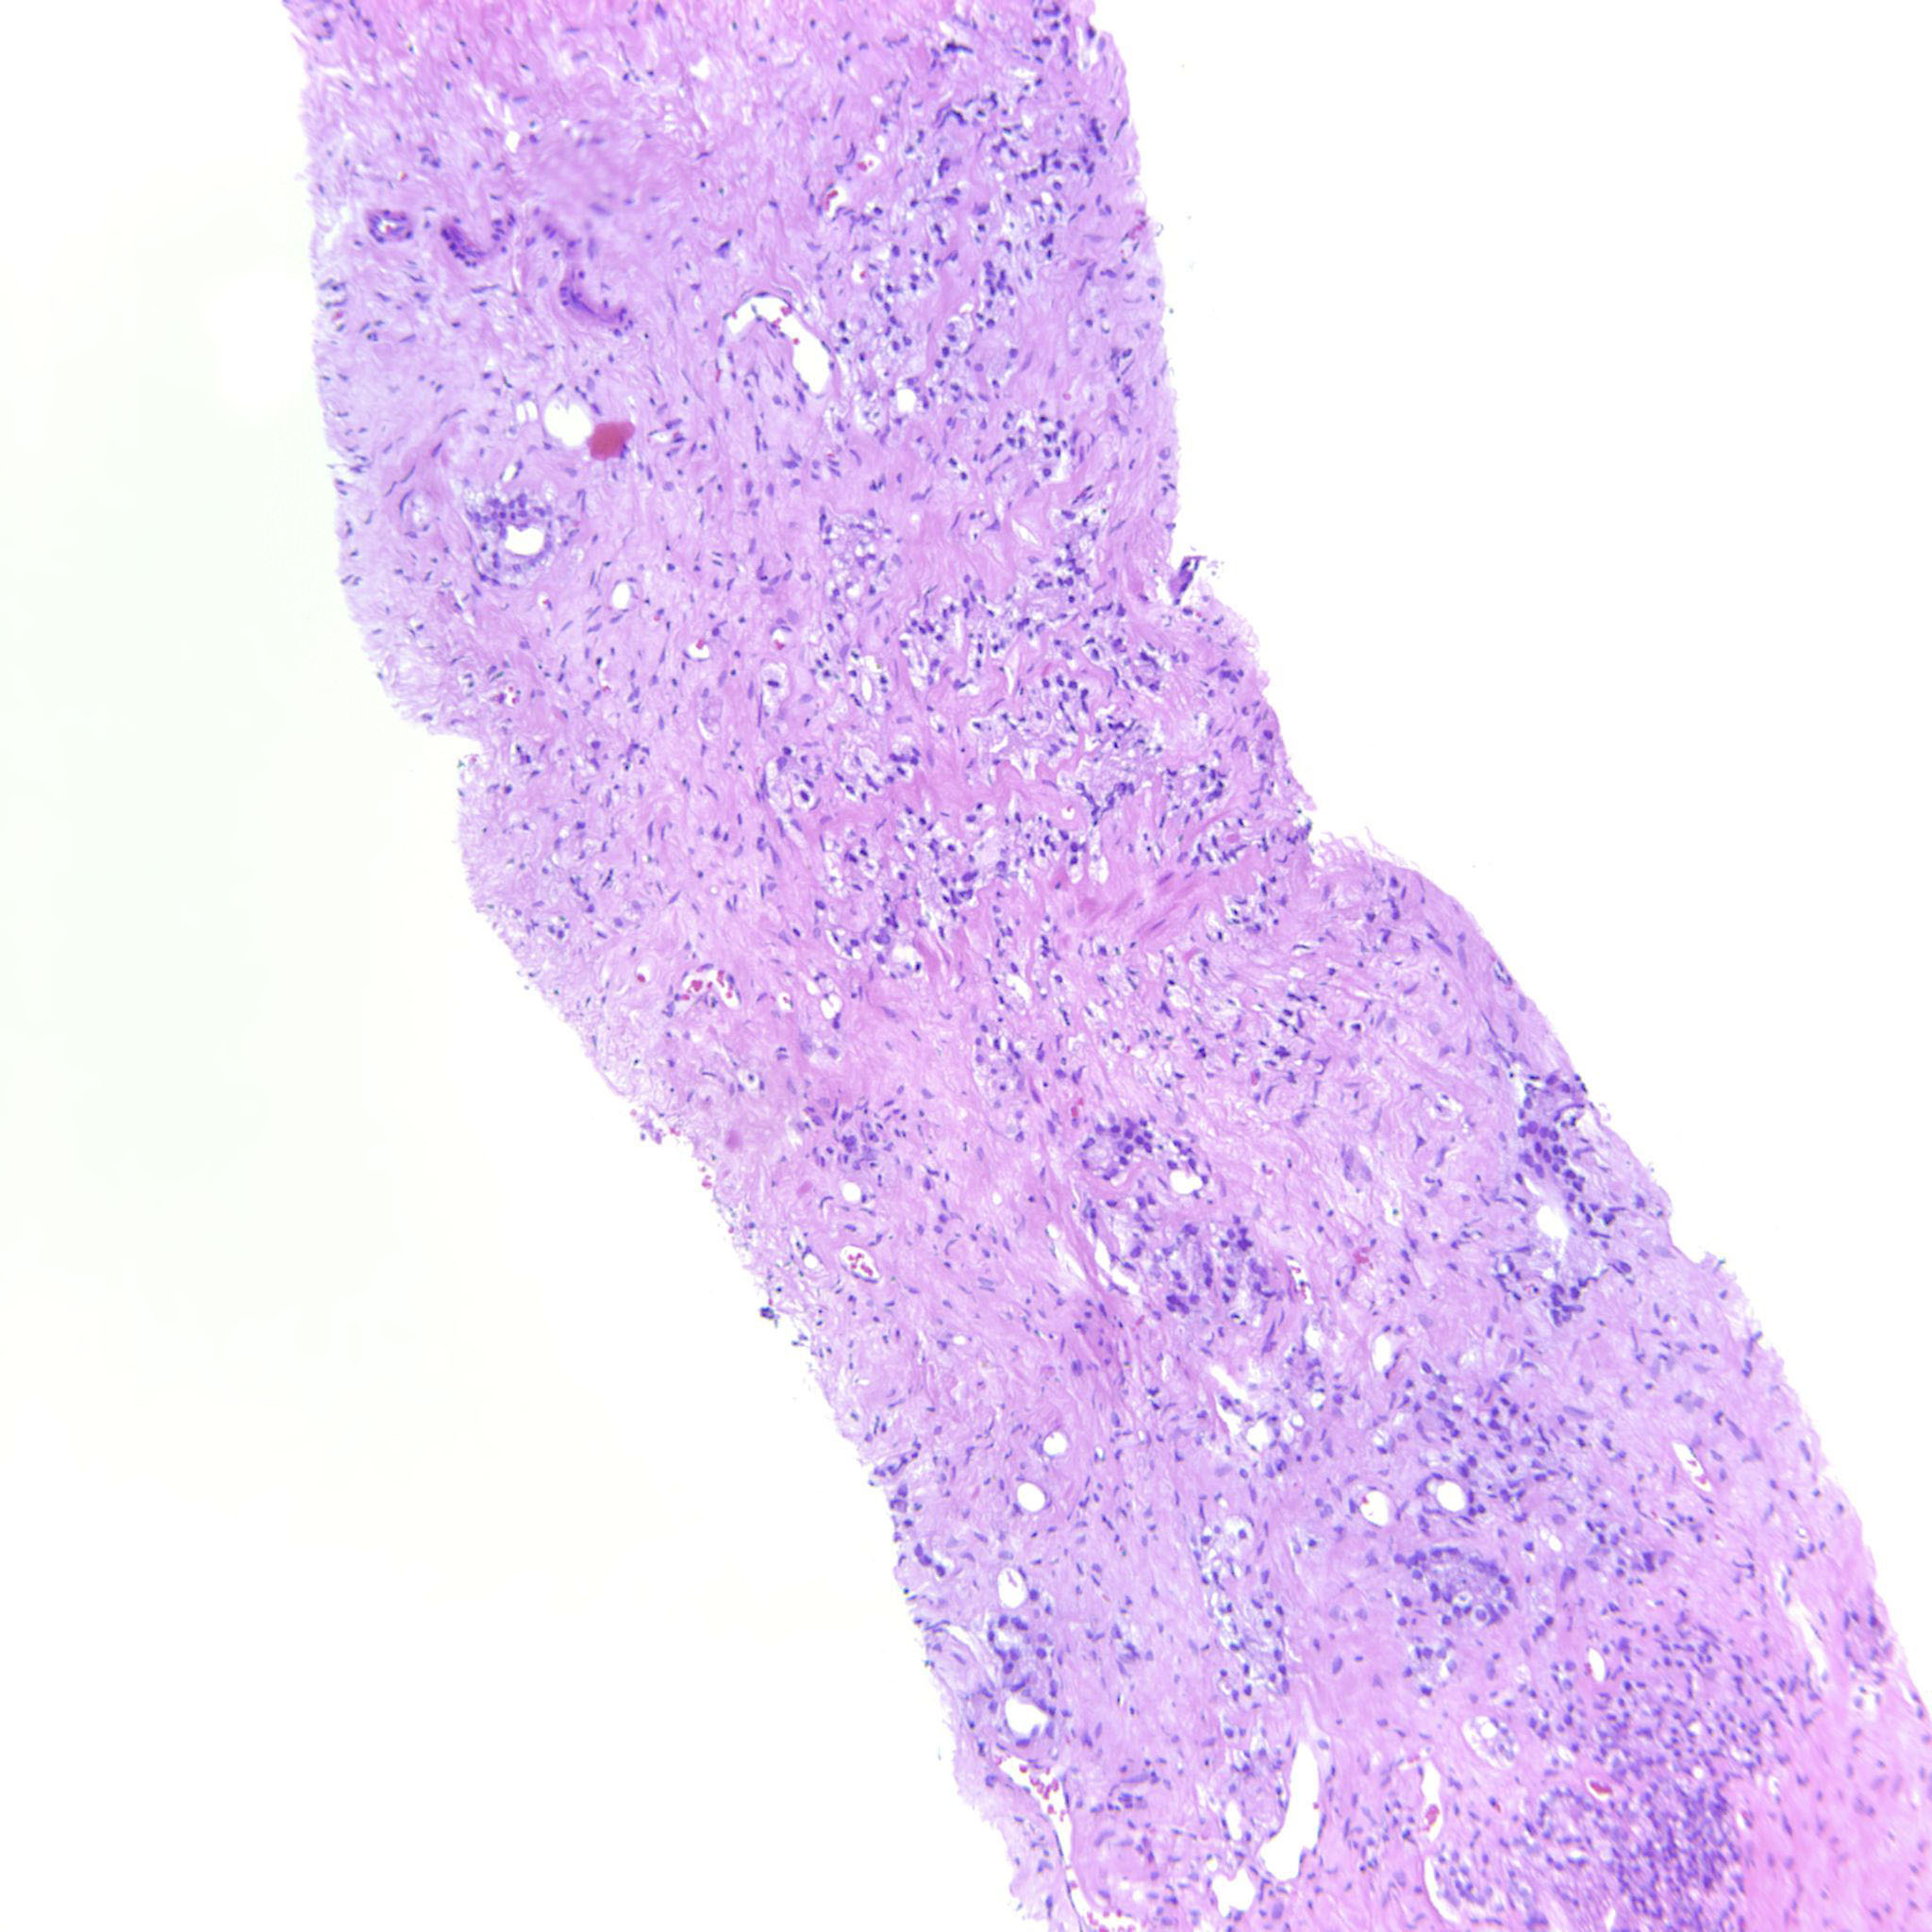

Prostate cancer grading

Case ID: 635